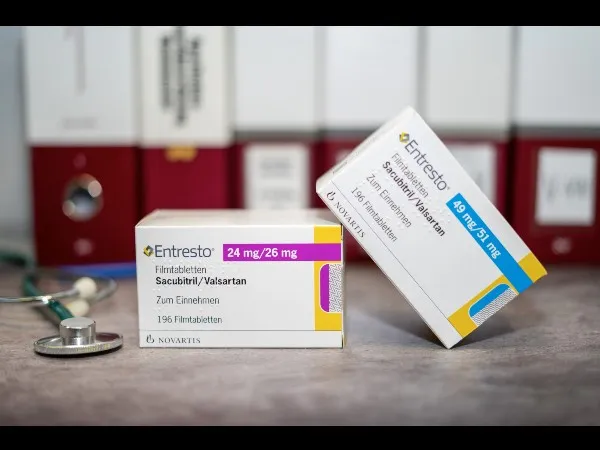

Resistência a diuréticos na insuficiência cardíaca: aumentar o diurético de alça ou associar tiazídico?

Resistência a diuréticos na insuficiência cardíaca: aumentar o diurético de alça ou associar tiazídico?